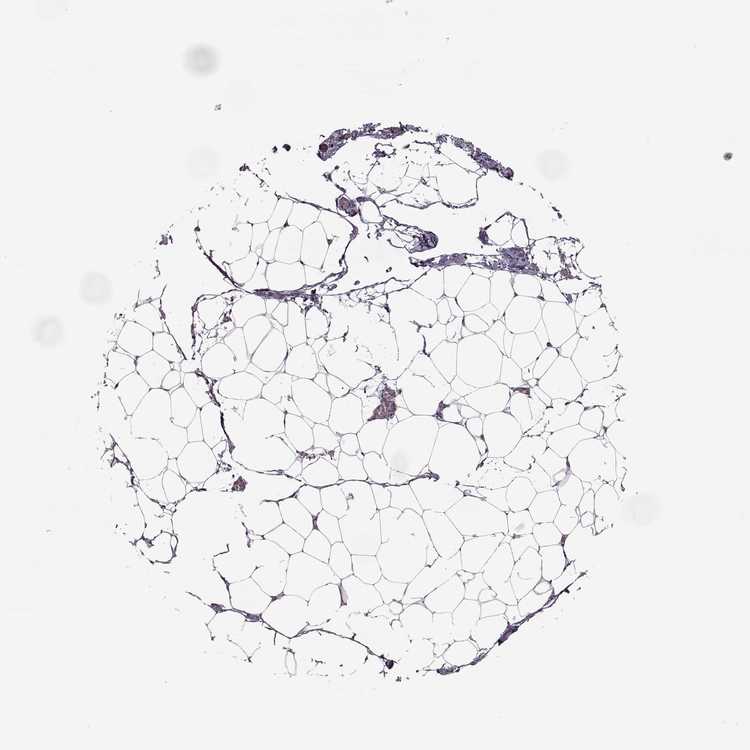

SOFT TISSUE 1 - Antibody stainingi

Antibody staining in the annotated cell types in the current human tissue is reported as not detected, low, medium, or high, based on conventional immunohistochemistry profiling in selected tissues. This score is based on the combination of the staining intensity and fraction of stained cells.

Each image is clickable and will lead to virtual microscopy that enables deeper exploration of all samples and also displays staining intensity scores, fraction scores and subcellular localization as well as patient and tissue information for each sample.

Antibody HPA023908

Chondrocytes Not detected

Fibroblasts Not detected